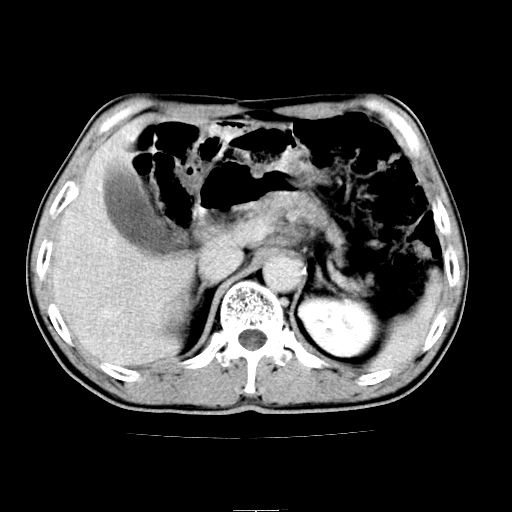

患者男,64岁,胃癌术后三个月,无明显不适。请讨论一下胰头前方小圆形低密度影为淋巴结还是肠管?

肠管吧.另外右肾见盂旁囊肿.

肠管.右肾见盂旁囊肿.

典型的无明显强化改变的淋巴结。

增强第6幅图上有气液平相通,是肠管,右肾低密度灶形态不规则似有壁结节,不除外转移.

胰头低密度影考虑是肠管

应该考虑是肠管,理由1、平扫和增强对比,形态和内部的密度有明显改变。2、增强图片可见明显气液平面。

是肠管影,肠壁有强化。